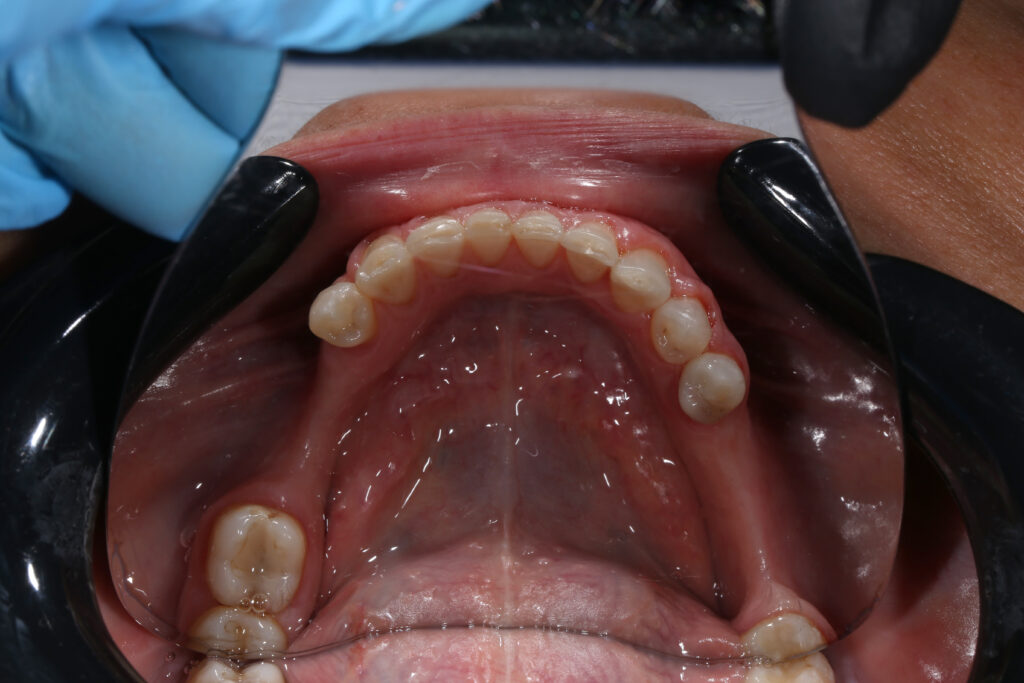

Ситуация до лечения

Из-за множественных давних удалений жевательных зубов, произошла деформация зубных рядов, зубы разъехались в область удаленных, что затрудняло протезирование в момент обращения к ортопеду.

Так же можно отметить сильное снижение высоты прикуса (верхние зубы на 100% перекрывали нижние, что вызывало хроническую травму десны), а также повышенную стираемость твердых тканей зубов, что является следствием повышенной нагрузки, которую много лет испытывали передние зубы, в связи с отсутствием жевательных зубов.